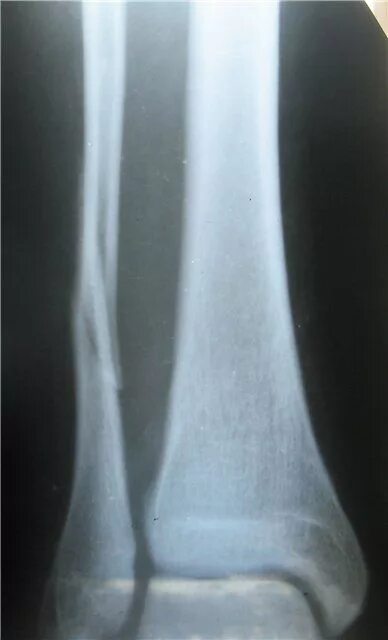

Сколько срастается малая берцовая кость